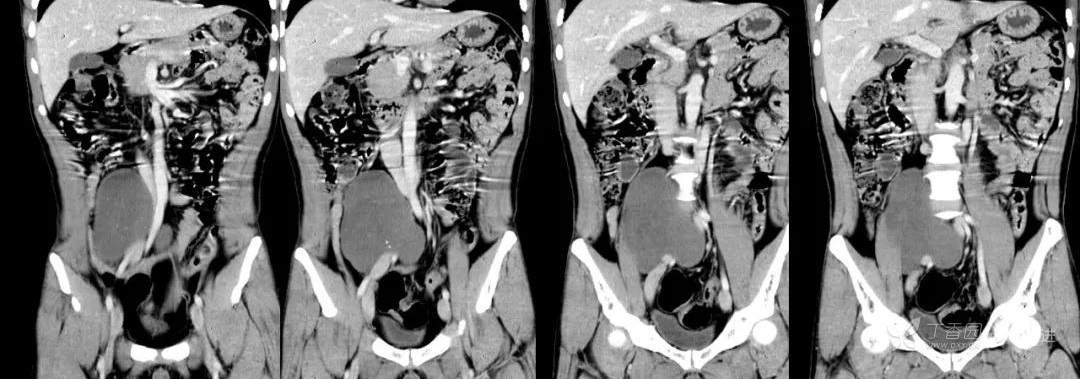

冠状位重建